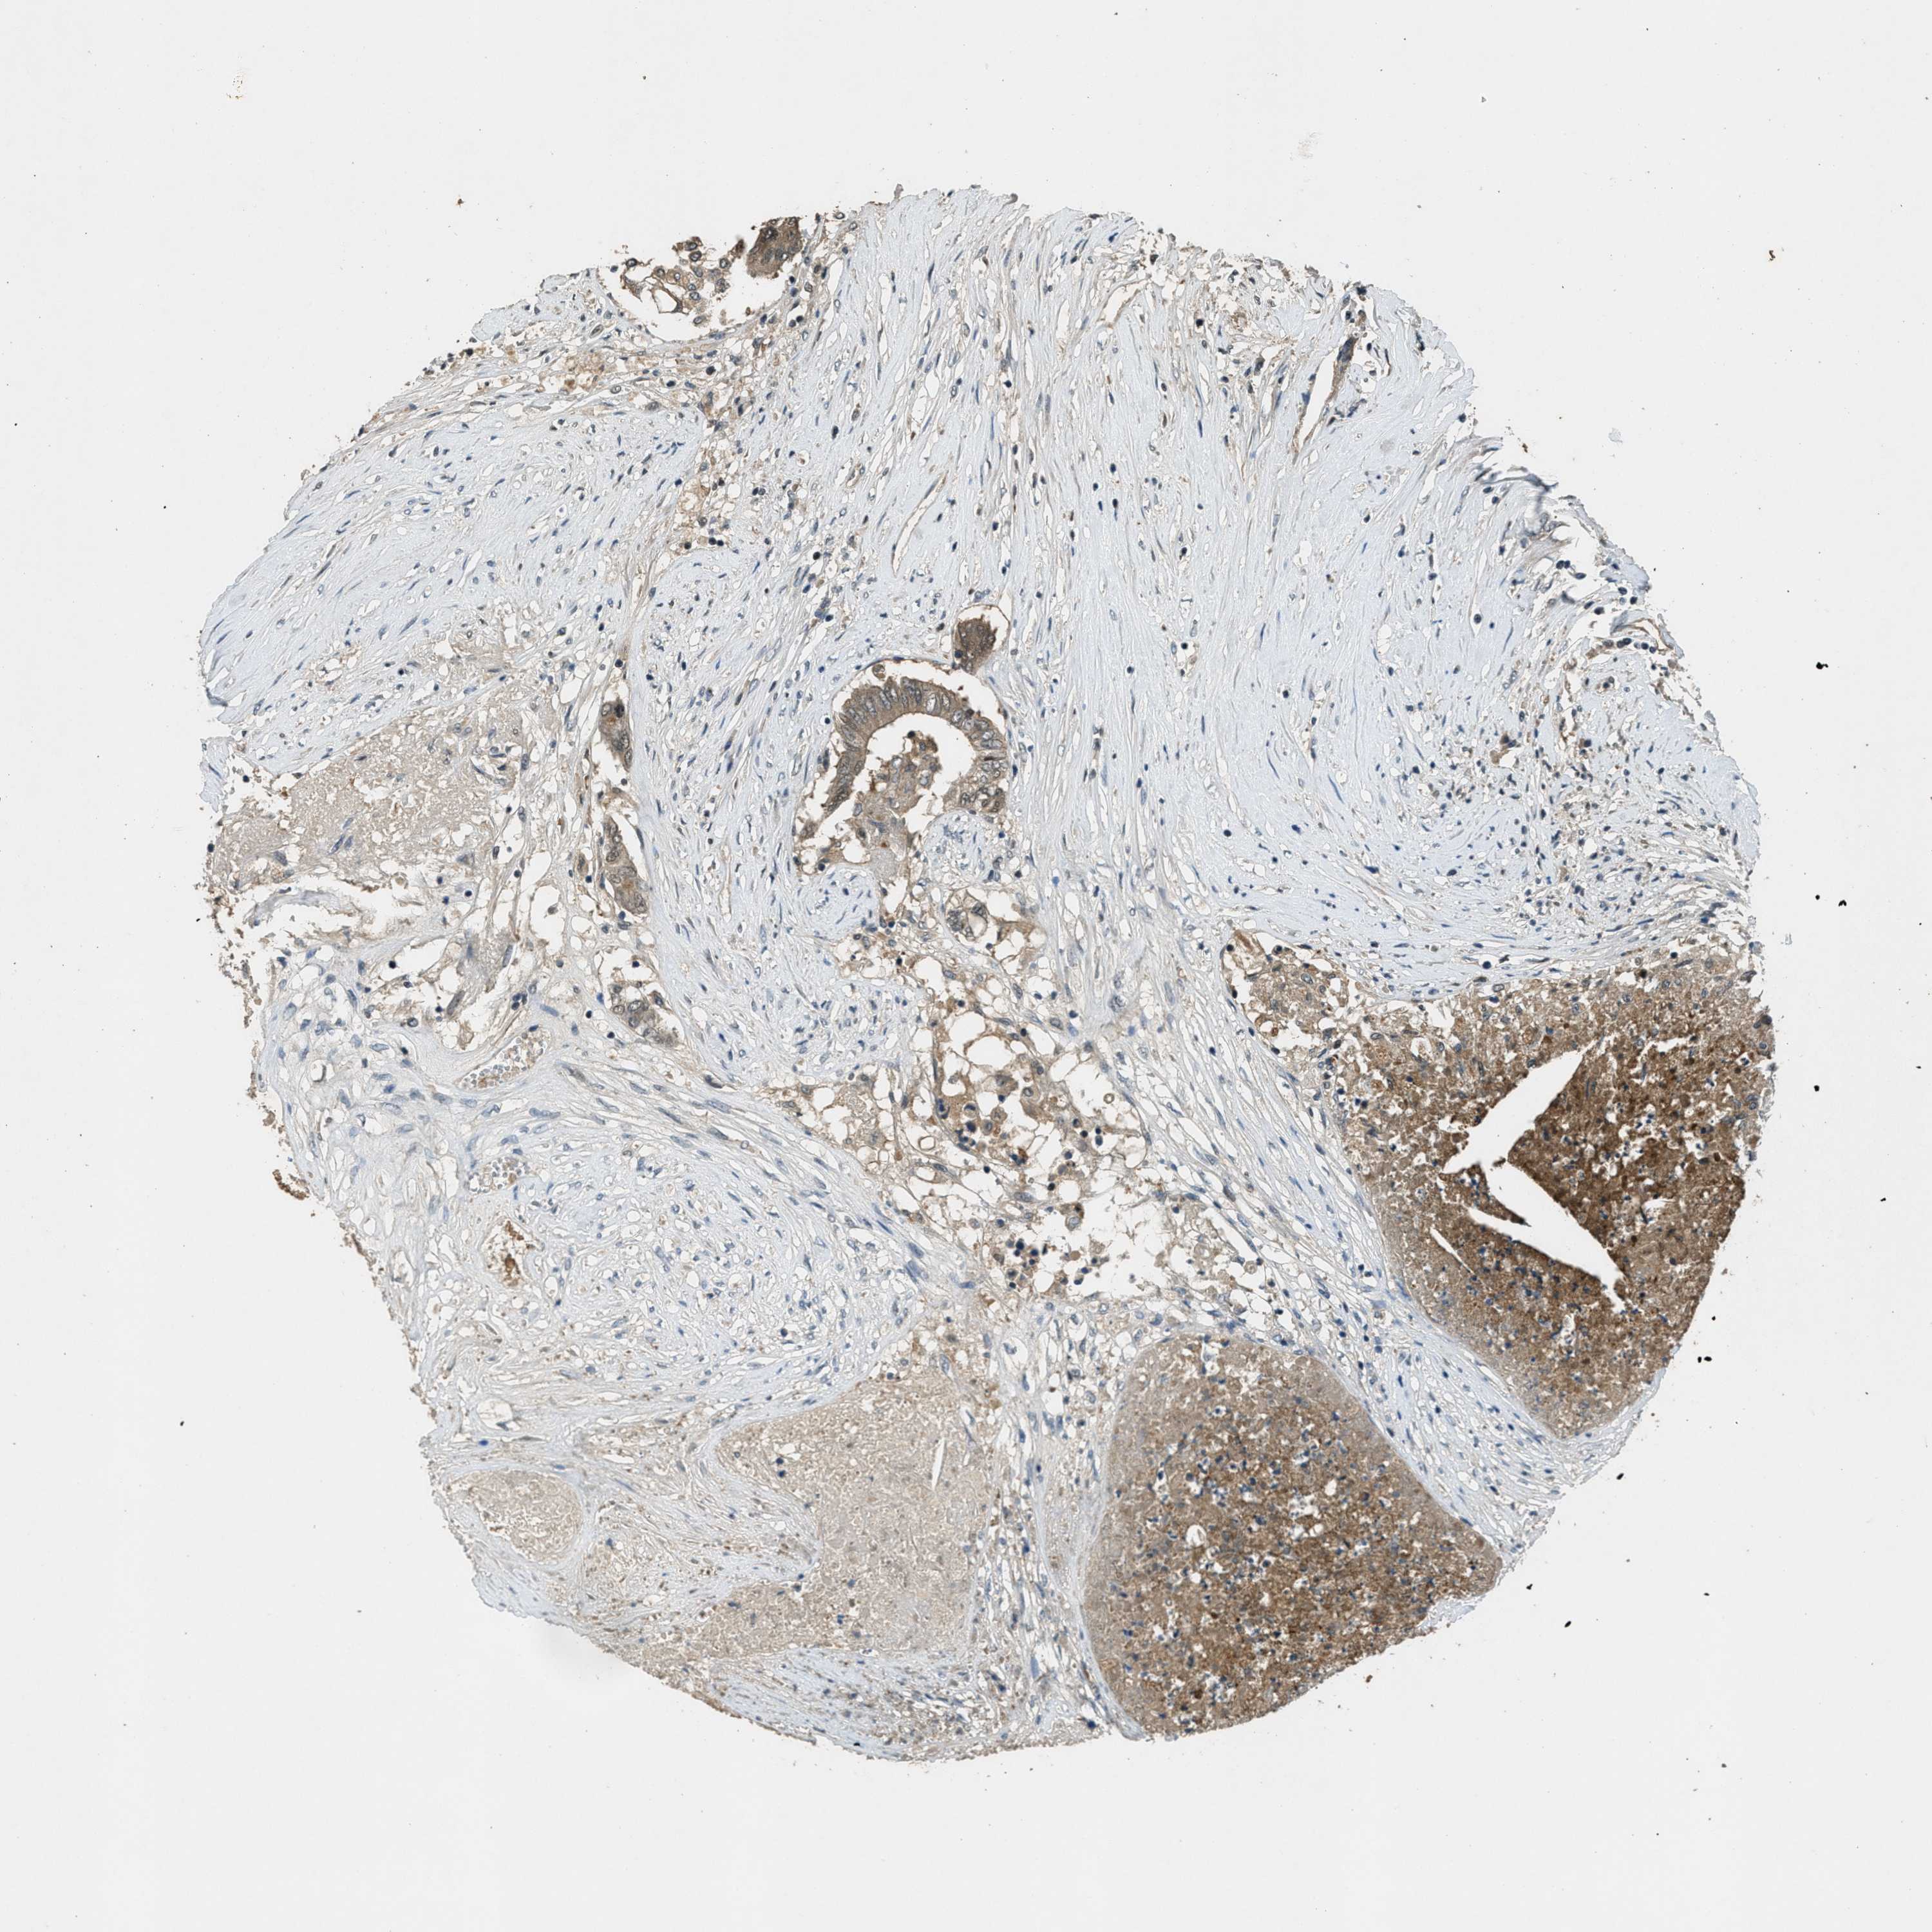

CANCER COLORECTAL CANCER Show tissue menu

Colorectal cancer

Human cancer

Colon adenocarcinoma